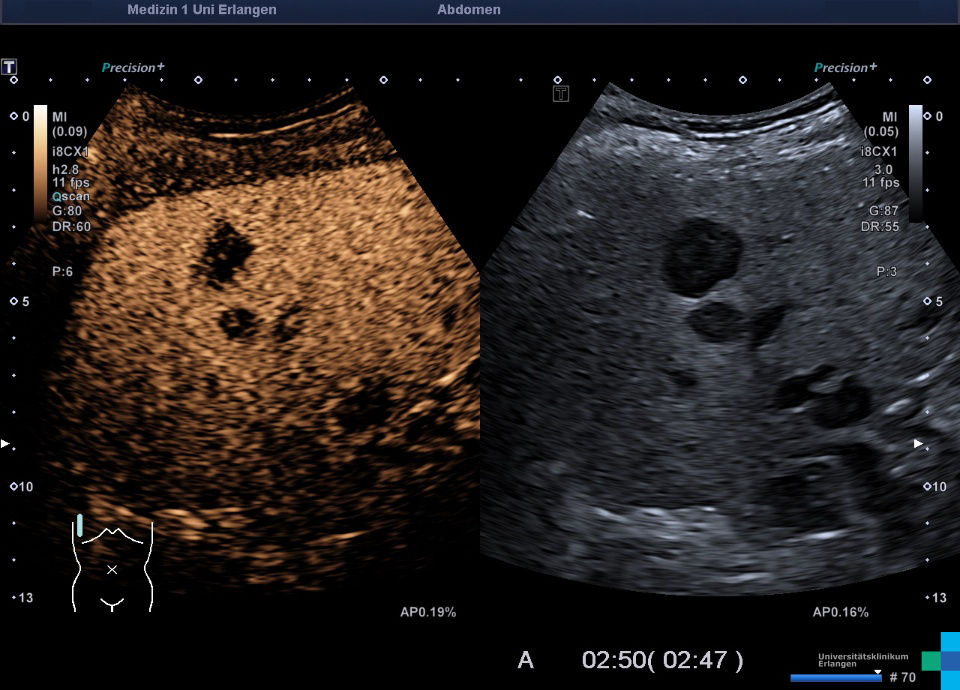

フィリップス、「Liver Fat Quantification(肝脂肪化定量評価。肝臓がん|消化器|診療内容|医療法人 甘木第一クリニック。肝臓がん|消化器|診療内容|医療法人 甘木第一クリニック。sakuraさん専用 蔵王吊るし柿4kg 紅干し柿 600g。Contrast Enhanced Ultrasound (CEUS) | フィリップスヘルスケア。Liver Ultrasonography | SpringerLink。キヤノンメディカルシステムズ、『肝臓の脂肪量の汎用超音波画像。Imaging Features of Hepatocellular Carcinoma in the Non。Imaging Features of Hepatocellular Carcinoma in the Non。714cFtk9QyL._AC_UF350,。肝臓病変における超音波の最新情報-第24回腹部放射線研究会。KMS_M01_XXX_670.jpg。腹部の超音波検査健康なヒト胆嚢 - 胆嚢のストックフォトや画像。